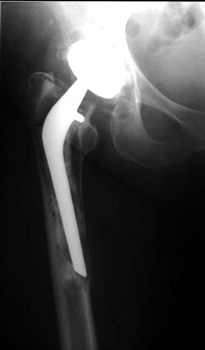

FEMORAL STEM POSITION

• Varus positioning

• Valgus positioning

Varus Normal Valgus